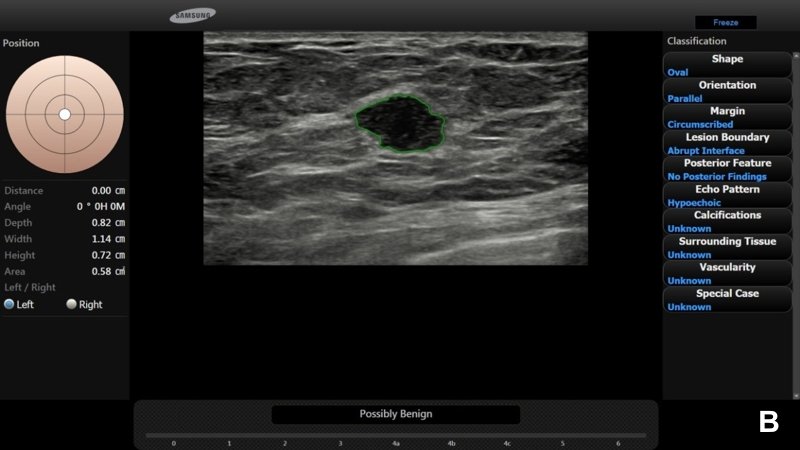

В прочих случаях для всех образований и радиологи, и программа S-Detect™ сделали предположения о доброкачественности (рис. 4).

УЗИ показало четко очерченное изоэхогенное образование овальной формы размером около 0,5 см (А).

И радиолог, и программа S-Detect™ расценили образование как вероятно доброкачественное (категория 3 по BI-RADS®) (В).